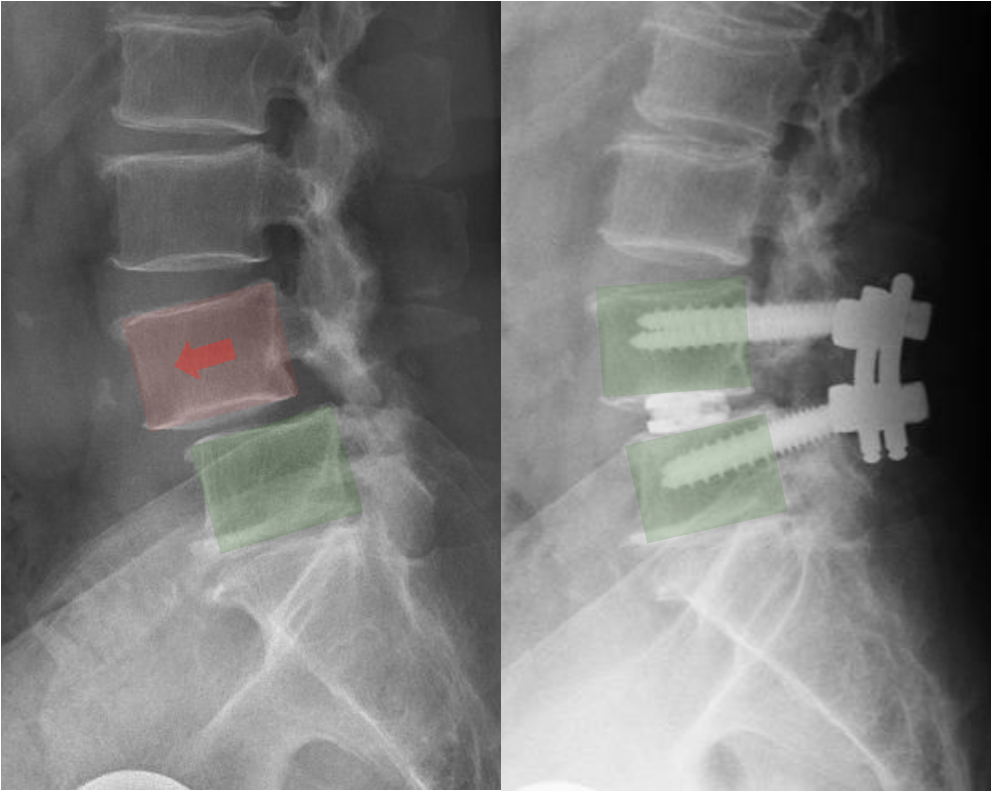

X-ray image of a human lumbar spine showing vertebrae and discs.

• X‑rays clearly show how much one vertebra has shifted relative to another.

• MRI shows nerves, discs, and areas of stenosis.

• Symptoms and nerve compression are often more important than the exact amount of slip.

X-ray image showing the cervical spine before and after spinal fusion surgery, with the right side displaying implanted screws and rods.